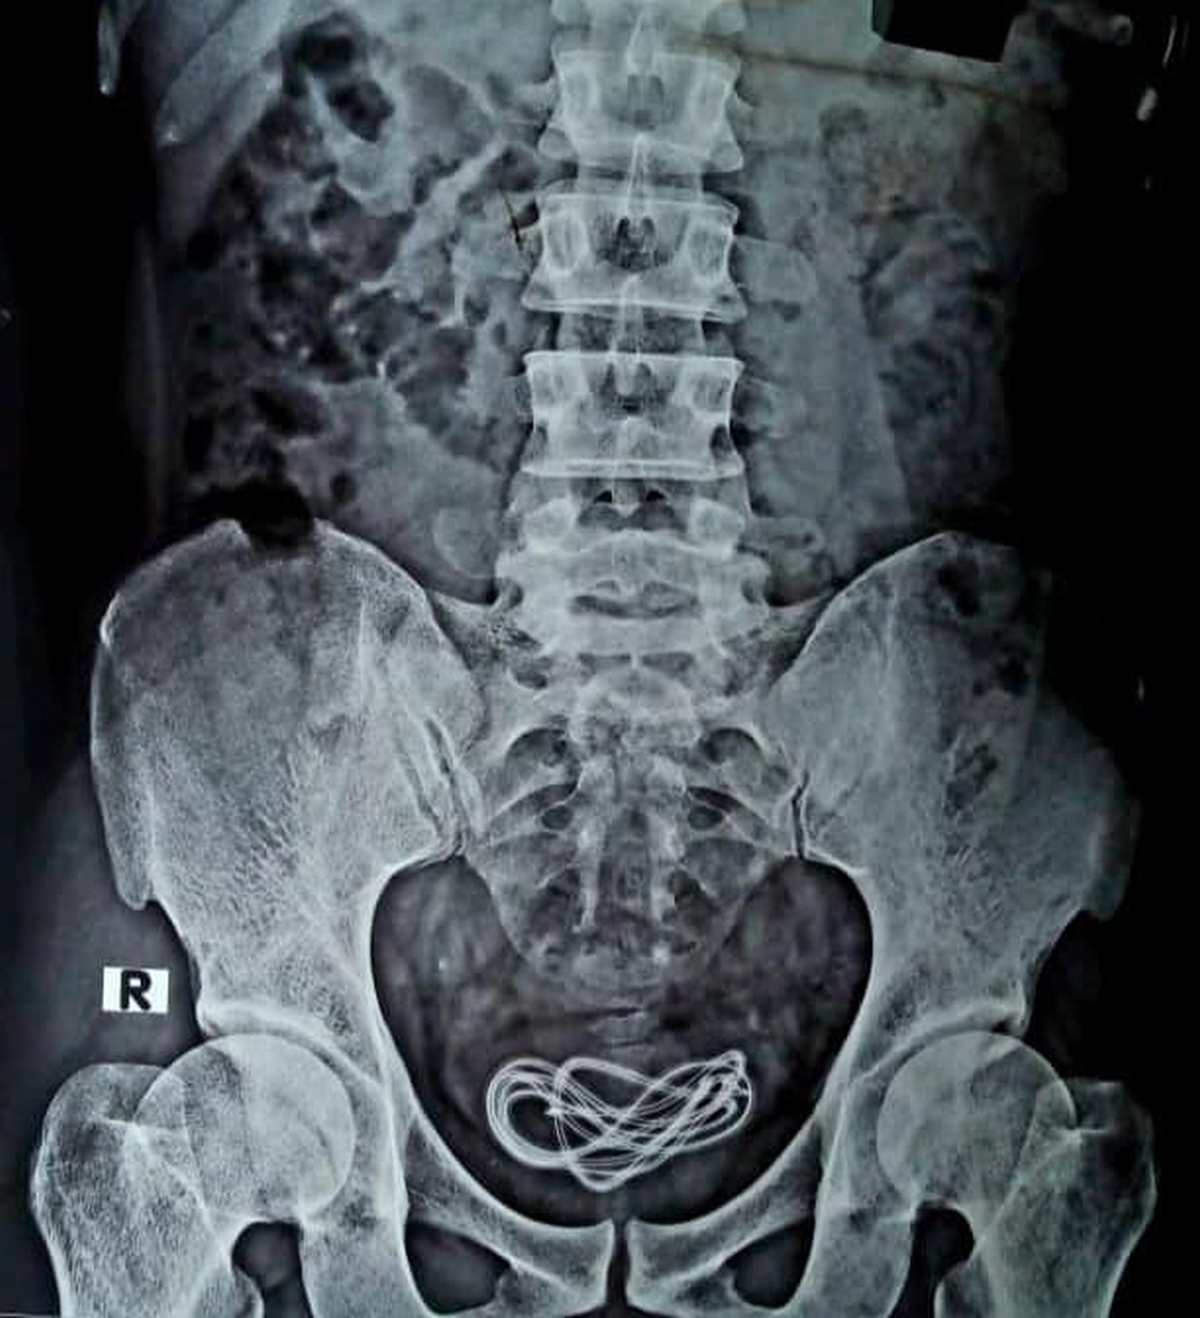

Upon operating, Dr Walliul Islam discovered a mobile phone charger inside the patient’s urinary bladder. And in a painful reveal, the surgeon explained that the phone charger—long cable included—found its way there via the patient’s urethra. The surgery was successful, although Dr Wallie questioned the mental health of the patient.

The 30-year-old patient reportedly has a spotted history with such incidents. The surgeon revealed that he had become “accustomed” to using cables and other devices into his penis to sexually gratify himself. However, he apparently lost control this time, and the entire cable—around 61cm in length—was lost into his bladder when he was pleasuring himself.